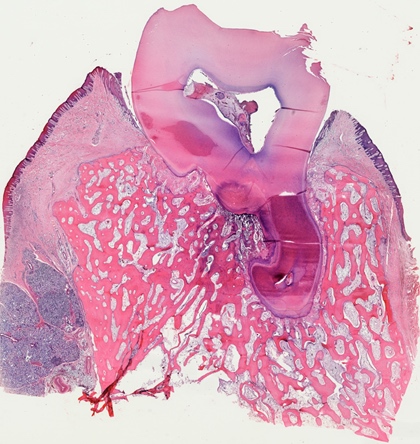

For almost two decades, we have provided prepared slides suitable for various biomedical courses. These glass slides contain sectioned, mounted, or smeared tissues stained with different methods.

They can be used to study histology, pathology, oral histology, oral pathology, embryology, microbiology, parasitology, and hematology.

Click the following categories to view example photos taken from these prepared slides.

The representative photos shown in each category are examples taken under the light microscope. They may not be the same ones as those available for your need. Complete lists of prepared slides for each course can be downloaded for further consideration.